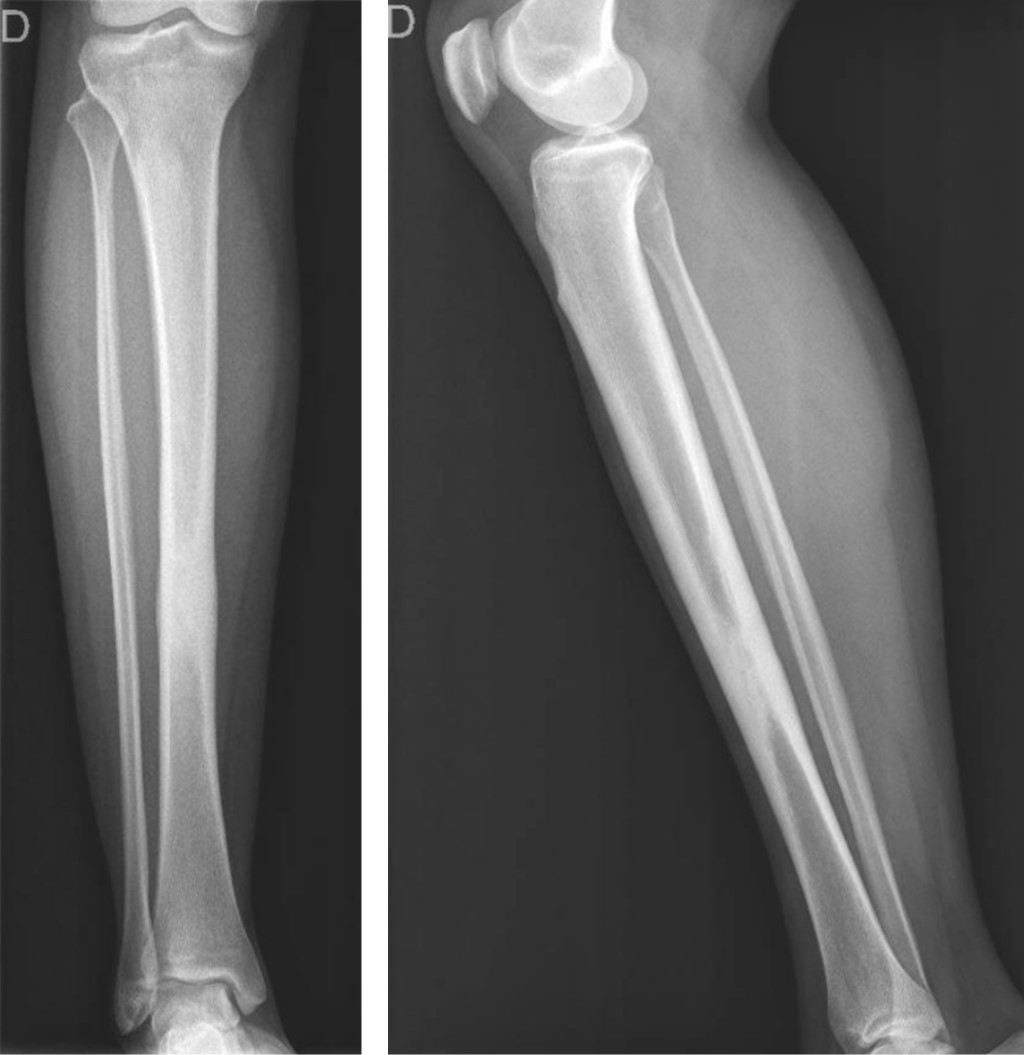

Se realizaron radiografías que demostraron una lesión intraósea diafisiaria única, de localización central, con bordes definidos, periostio engrosado pero sin interrupción y sin signos de malignidad. No se observó afectación de los tejidos blandos ni destrucción ósea adyacente (Figura 1). La resonancia magnética confirmó los hallazgos descritos; la lesión se caracterizó como inespecífica, con apariencia esclerosa y ocupación de toda la cavidad medular, con engrosamiento de ambas corticales (Figura 2). Se realizó una gammagrafía ósea que demostró una posible reacción osteogénica avanzada con evidencia de patología inflamatoria secundaria a destrucción ósea. Se realizó una biopsia incisional cerrada, que descartó lesiones infecciosas o neoplásicas.

El diagnóstico de la enfermedad se realiza mediante radiografía simple, tomografía, resonancia magnética, gammagrafía ósea y biopsia, excluyendo otras posibles condiciones. En las pruebas de imagen se observa un engrosamiento cortical de la diáfisis de los huesos largos y, en ocasiones, un estrechamiento del canal medular. La resonancia magnética confirma la presencia de esclerosis y revela edema de la médula ósea en la diáfisis.3 La gammagrafía ósea es útil para determinar la extensión de la enfermedad y para planificar la obtención de muestras de tejido. La biopsia puede ayudar en el diagnóstico diferencial y mostrar actividad histológica osteoblástica.

Figura 2